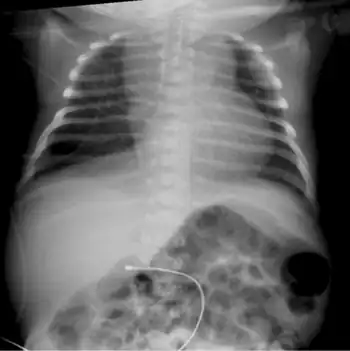

| Infant male with the brachytelephalangic type of chondrodysplasia punctata | |